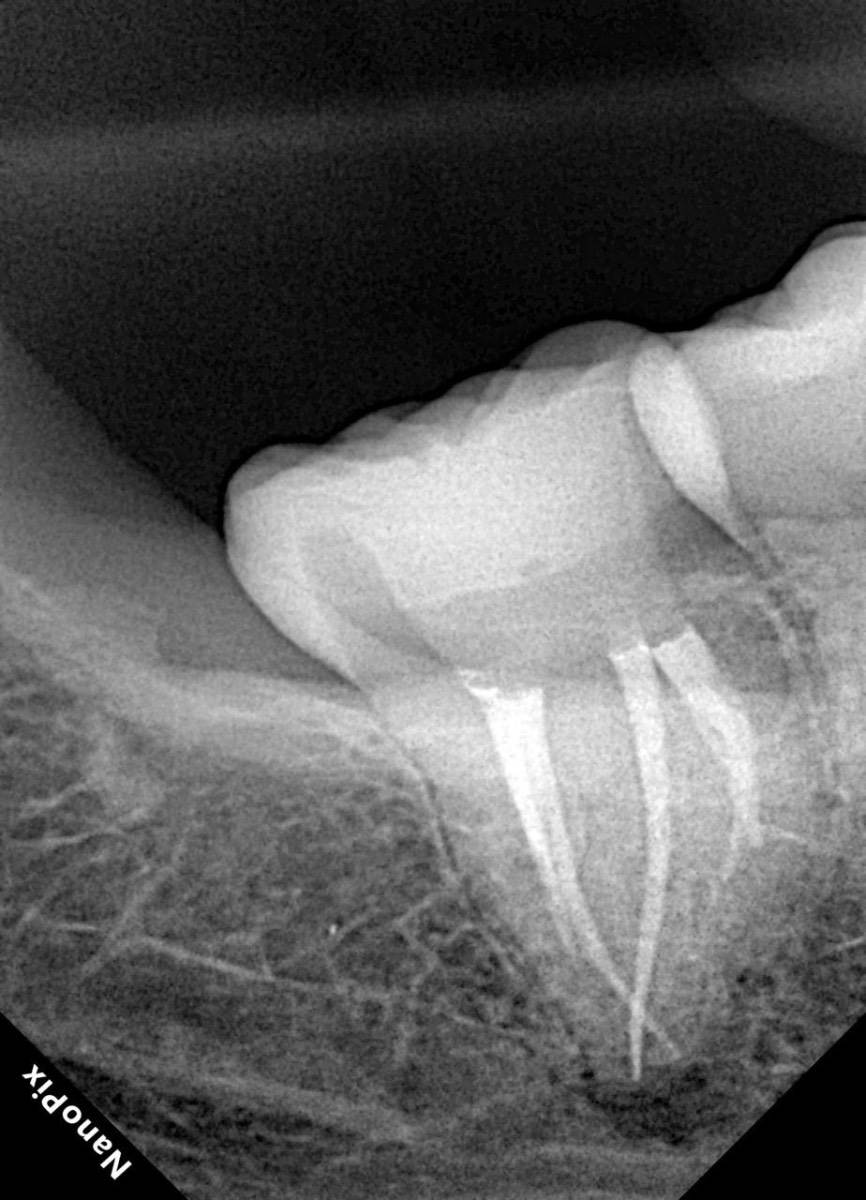

Гарриевич Опубликовано 18 марта Автор Поделиться Опубликовано 18 марта В 13.03.2026 в 15:26, Doc сказал: Круто! То, что вынимается, доктору вернуть надо или в металлолом сдать? :))) Обычно мы сдаем в чернмет, какие никакие деньги)) Реколл 3 года 1 Ссылка на комментарий

Гарриевич Опубликовано 10 часов назад Автор Поделиться Опубликовано 10 часов назад Еще один осмотр спустя 3 года и полное заживление 1 Ссылка на комментарий

Doc Опубликовано 46 минут назад Поделиться Опубликовано 46 минут назад 9 часов назад, Гарриевич сказал: Еще один осмотр спустя 3 года и полное заживление Круто, как обычно! Ссылка на комментарий